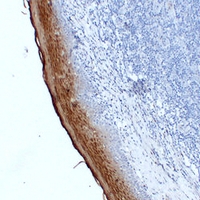

(Immunohistochemical analysis of Annexin A1 staining in human esophagus formalin fixed paraffin embedded tissue section. The section was pre-treated using heat mediated antigen retrieval with sodium citrate buffer (pH 6.0). The section was then incubated with the antibody at room temperature and detected using an HRP conjugated compact polymer system. DAB was used as the chromogen. The section was then counterstained with haematoxylin and mounted with DPX.)